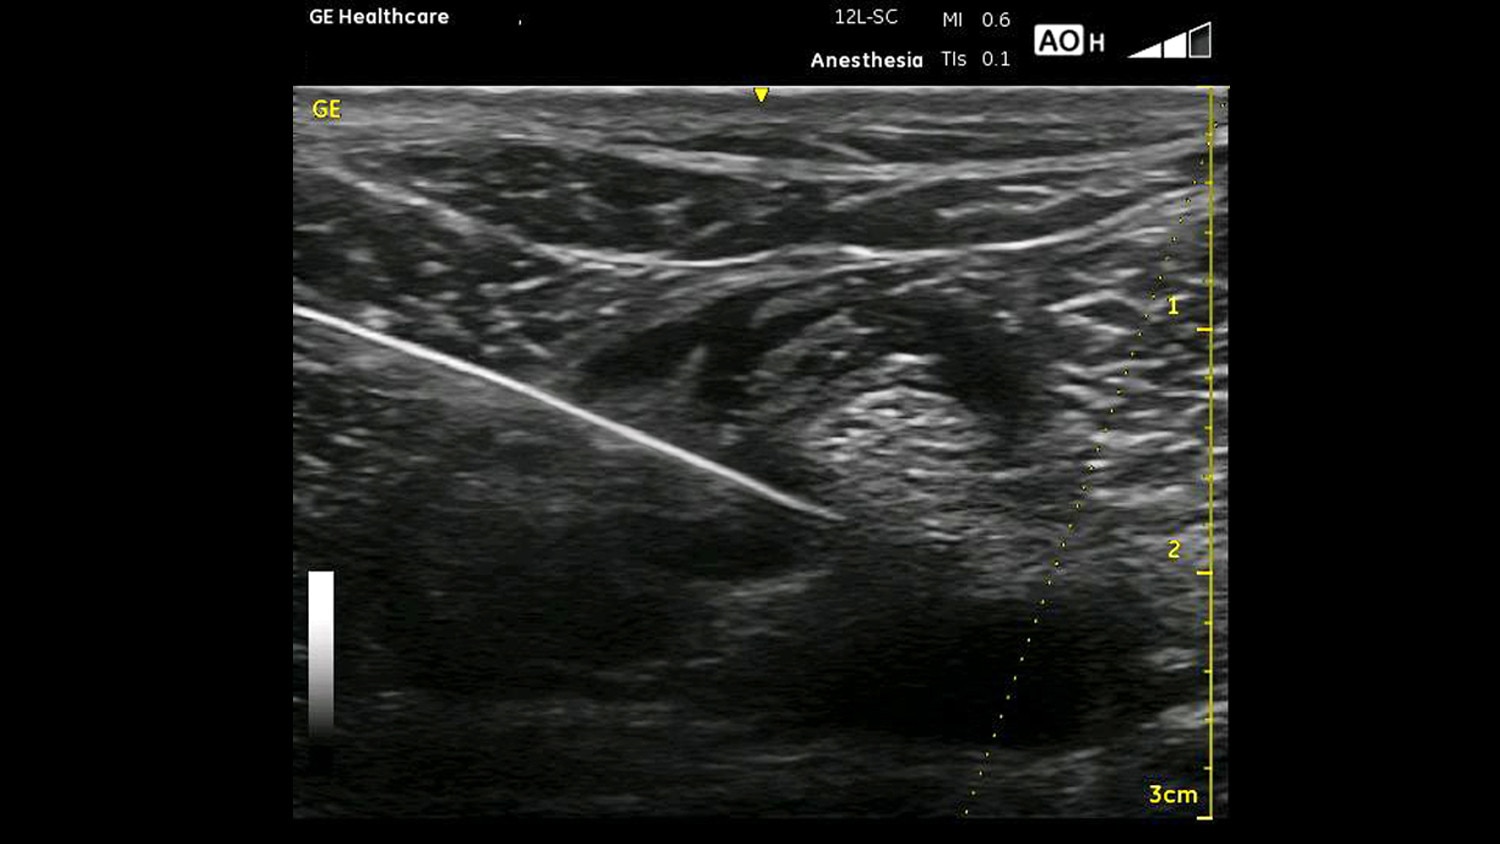

Regional Anesthesia and Chronic Pain

Clinical Images

Regional Anesthesia